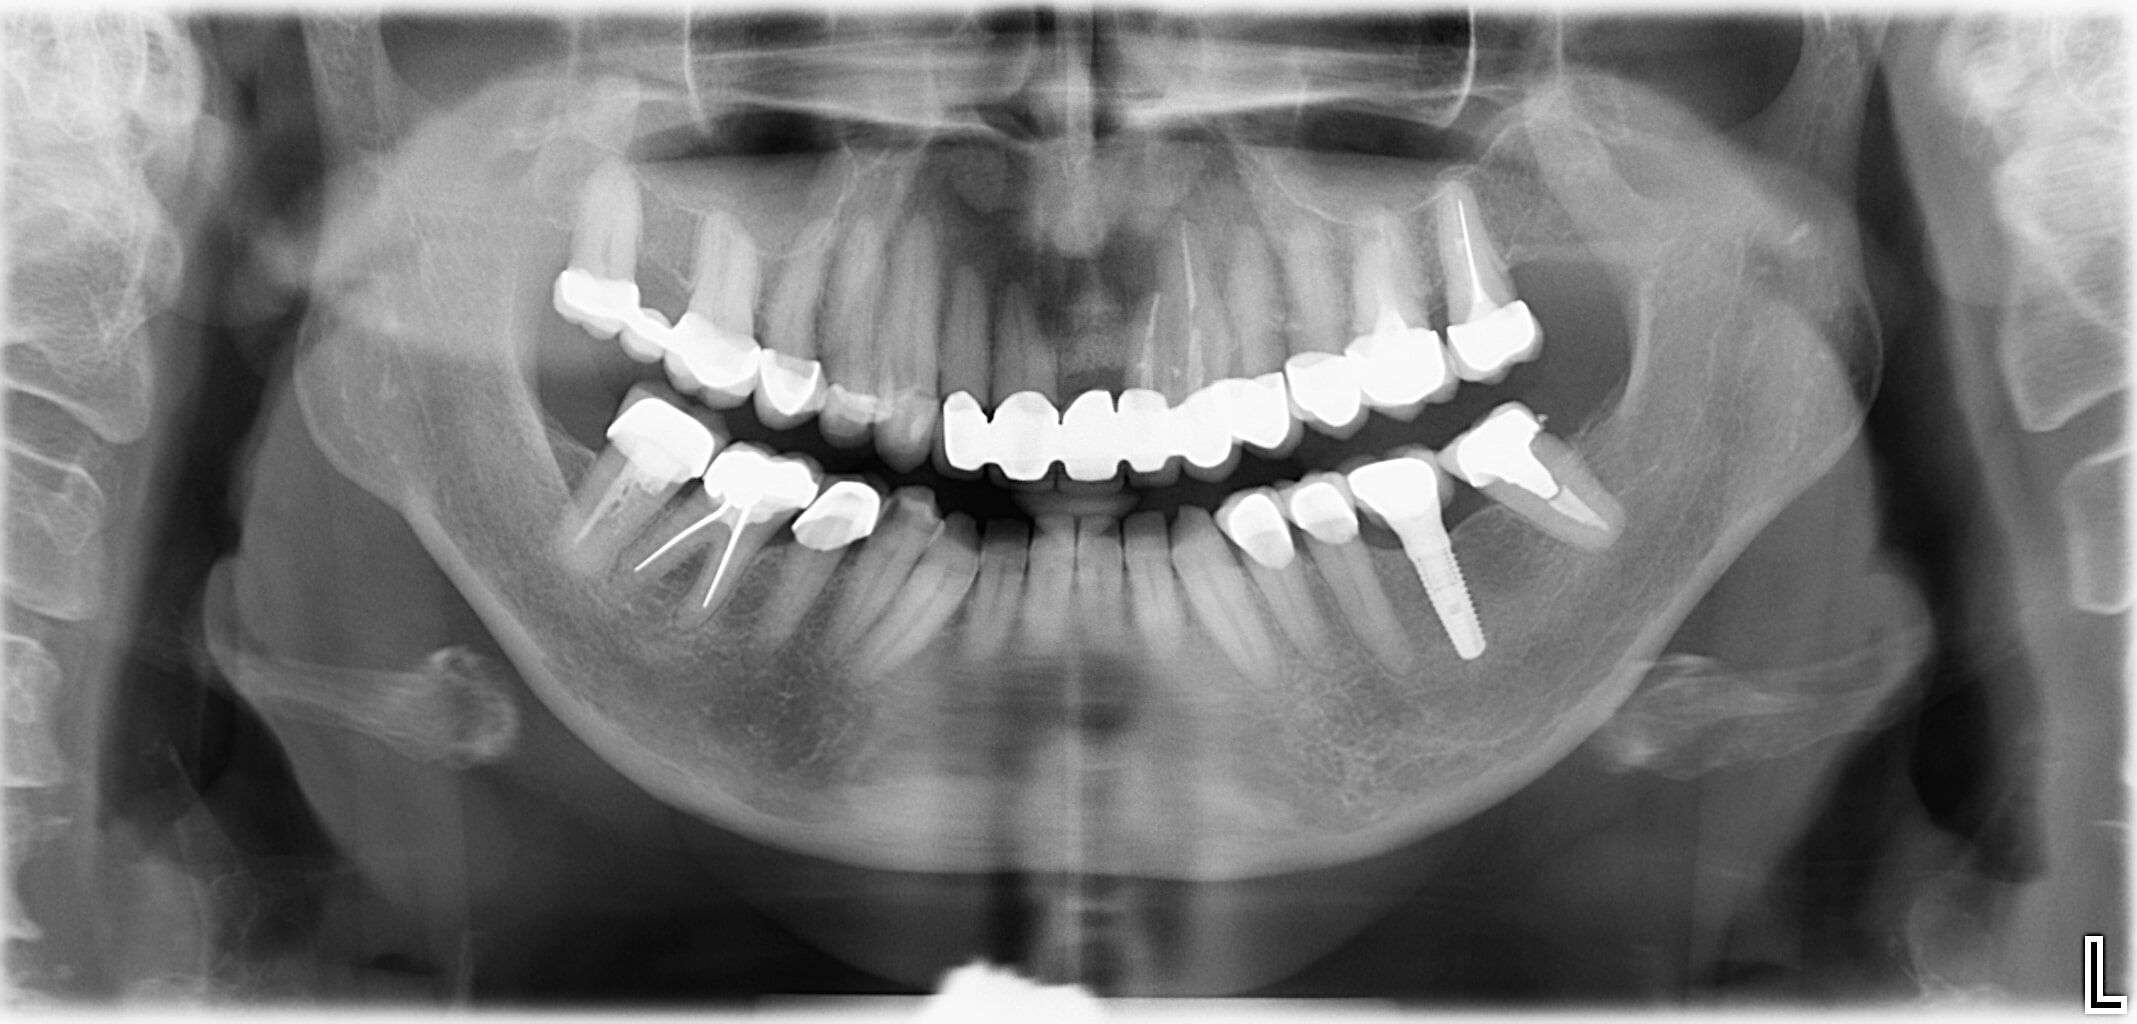

Für Patienten mit chronischen Erkrankungen, Allergien oder Unverträglichkeiten und dem Wunsch nach einer metallfreien Implantation, sind Keramikimplantate eine Alternative zu Titanimplantaten. Keramikimplantate sind 100 % biokompatibel und zeichnen sich durch hohe Verträglichkeit, optimale Einheilung im Kieferknochen, lange Lebensdauer und ausgezeichnete Werkstoffeigenschaften aus. Keramikimplantate sind grundsätzlich für jeden Patienten nach Abschluss des Kieferwachstums geeignet.

Keramikimplantate werden aus dem metallurgischen Werkstoff Zirkonoxid hergestellt und mit Keramik oberflächenvergütet und gelten als biologisch voll verträglich. Heute kommen zwei verschiedene Varianten von Keramikimplantaten zum Einsatz, sogenannte einteilige Varianten und zweiteilige Varianten.